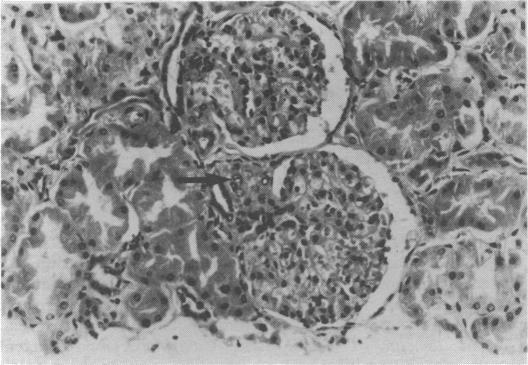

Immunodeficiency and cryptosporidiosis. Demonstration at the Royal College of Physicians of London.

Br Med J. 1980 Oct 25;281(6248):1123-7. doi: 10.1136/bmj.281.6248.1123.